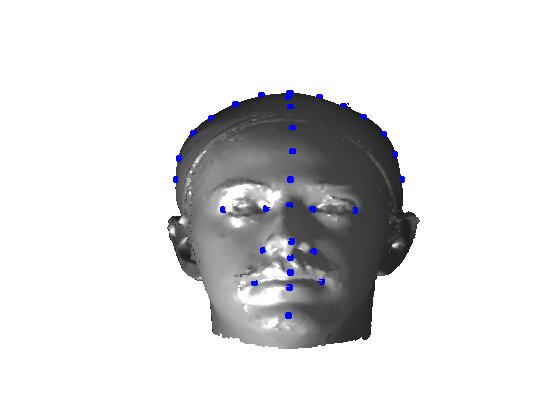

The landmarking system that we have implemented is a modified version of Creusot et al [23], where landmark candidates are generated via per-landmark scoring functions and then a configural model is iteratively fitted using a sample-consensus scheme. There are two parts to this algorithm: an off-line training scheme, shown in Fig. 5 and an online landmarking scheme, shown in 6. Note that we consider a sparse model of the face to consist of a set of landmarks in paticular configuration along with a set of landmark detector functions that score the likelihood of a particular vertex being a particular landmark, based on its local shape.

Referring to Fig. 5, our method is a supervised learning technique - landmarks are marked by hand on a set of training images. We used 279 faces (each different individuals) in the Face Recognition Grand Challenge (FRGC) dataset [26]. The landmarks used are described in table 1 111Some descriptions taken from www.facebase.org and can be seen on an example FRGC 3D face scan in Fig. 7.

Fig. 9 shows examples of the fitted model (trained on FRGC data) on the first four subjects in our Headspace training set. Note that the mean of the landmarks in the sparse model is centred on the orgin, and so the scan data is moved towards that and becomes frontal in pose. We note that other researchers [28] have used 3D landmark localisation to find the head, but often this only includes landmarks that are relatively easy to localise, namely inner eye corners and nose. Localising more landmarks over a wider facial area has a number of advantage in terms of cropping, pose normalisation and global 3D template warping, all of which are described later.